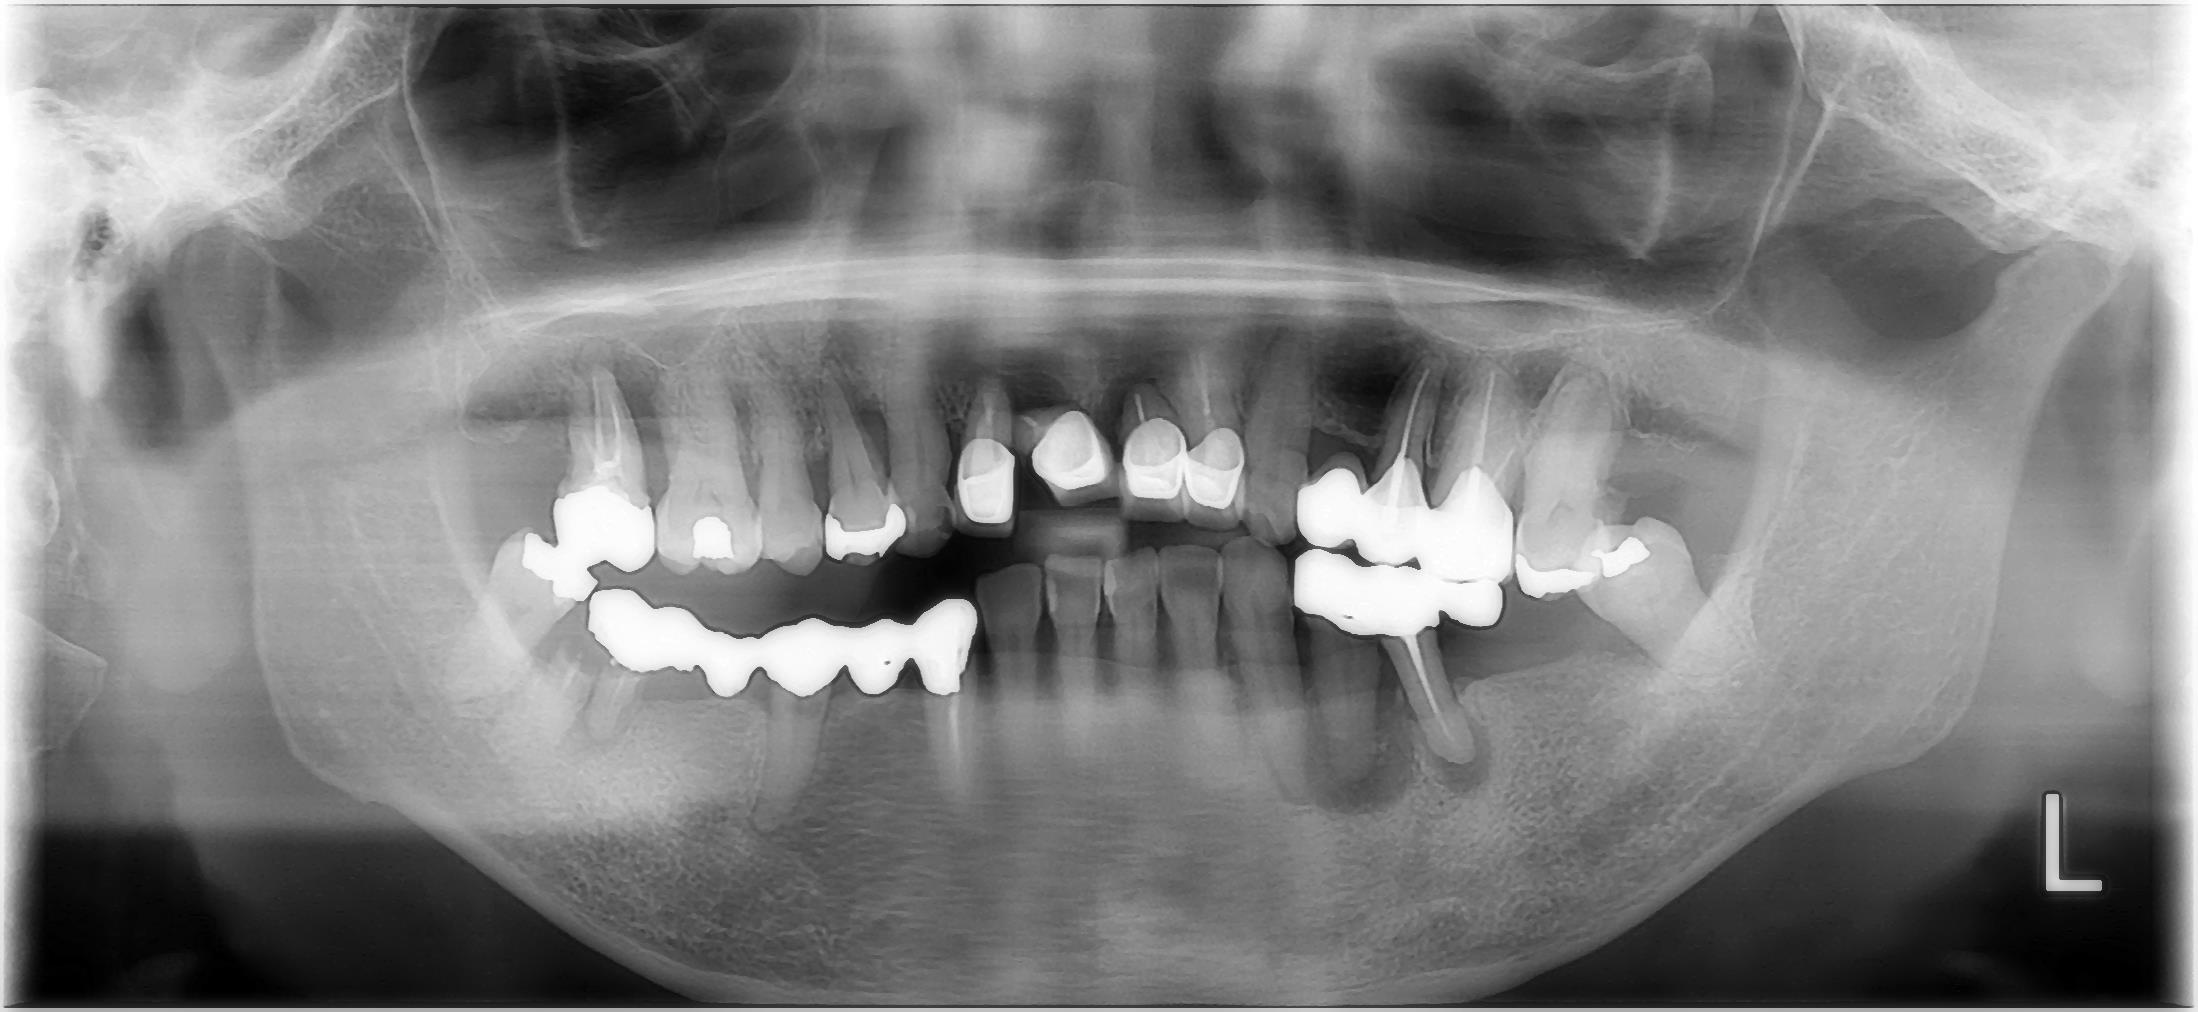

治療前

| 治療内容 | 抜歯 咬合挙上 セラミック治療 |

| 治療期間 | 6か月 |

| 費用 | セラミック治療485,100円(税込み) インプラント治療1409,650円(税込み) |

| 治療のリスク | 稀に割れることがあります。 |

| 所見 | 治癒に合わせて治療を行うため、仮歯の期間も長かったが、根気つよく真面目に通って頂けたおかげで安定した口腔内を確立できた。 |